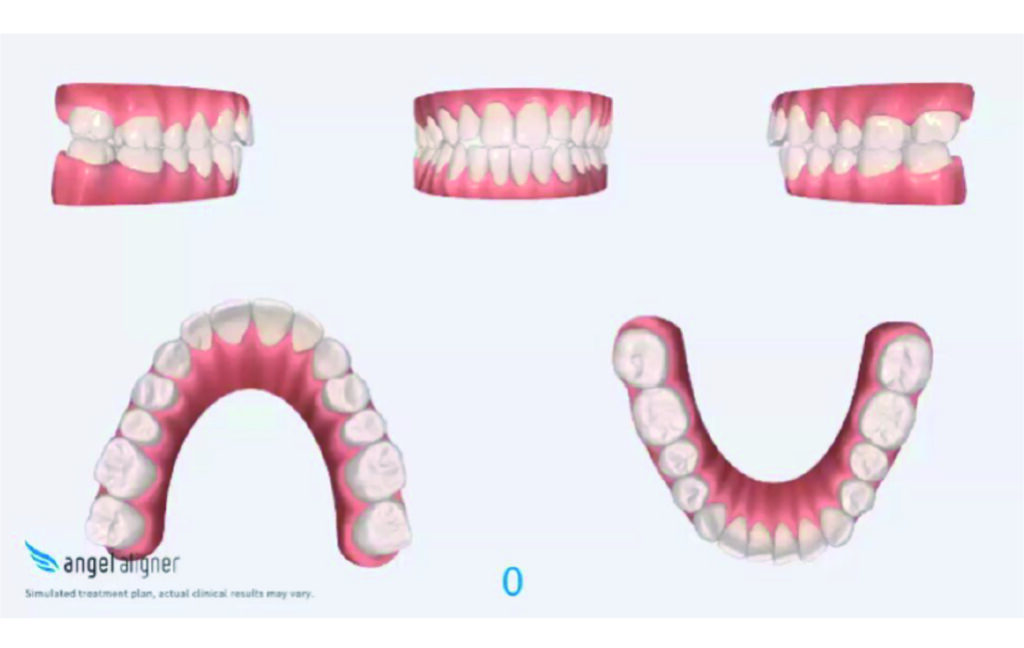

Initial Photos and datas

Clinical examination and diagnosis

Angle Class II 2mm on the right, Angle Class II 2mm on the left, light mandibular asymmetry to the right, lower central line 1mm to the right, upper central line 1,5mm to the left, 1mm overjet and overbite. Sagittal asymmetry of upper dental arch. Light crowding upper and lower frontal segments, severe attrition of posterior teeth, night bruxism. Normal sagittal position of both jaws, high angle case, steep mandibular ramus,excessive lower facial height, open bite tendency.

The case initially presented as a moderate Class II on the right and a Class II tendency on the left, with tapered dental arches and an anterior open bite extending to tooth 26 in segment II.

In segment I, the open bite reached up to the first premolar.

A 1.5 mm deviation of the upper dental midline to the patient’s left was noted, along with a slight mandibular midline shift to the right, likely due to asymmetrical mandibular growth observed in the facial structure. Severe mesial rotations of teeth 16 and 26 were evident in the initial records. As derotation of 16, 26, 17, and 27 progressed up to aligner 16, the premolars in segments I and II moved distally, resulting in a bilateral Class I relationship, as intended in the initial treatment plan.